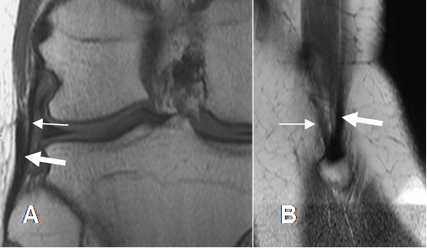

La valoración con Rx de los meniscos solo permite determinar su calcificación, en casos de condrocalcinosis. Disminución o cambios degenerativos en los espacios femorotibiales, hacen sospechar su compromiso. (5).

En la actualidad la RM es la modalidad de elección para valorar su lesión, utilizando secuencias sagitales. En casos de contraindicación, la artroTAC, es una buena alternativa.

Los cuernos anterior y posterior, se identifican como estructuras triangulares, hipointensas y de bordes bien definidos. (5). (Fig 29 a 32).

La artroresonancia (ArtroRM) es la mejor técnica para evaluar la rodilla postquirúrgica y los cambios meniscales y del LCA.

La aplicación de la mezcla intra-articular de contraste, se hace en la misma mesa de examen, dirigida por palpación y puncionando la parte inferior del borde lateral de la patela.

Fig 29. Meniscos normales.

A: RM sagital en T1, B: RM sagital en T2 y C: ArtroRM sagital en STIR. Meniscos normales triangulares e hipointensos en todas las secuencias. Cuernos anteriores (Flechas delgadas) y cuernos posteriores (Flechas gruesas).

Fig 30. Meniscos normales.

A: RM coronal en STIR. Menisco interno (Flecha delgada) y menisco externo (Flecha gruesa). B: RM axial en T2. Menisco interno (Flechas delgadas) y Externo (Flechas gruesas).